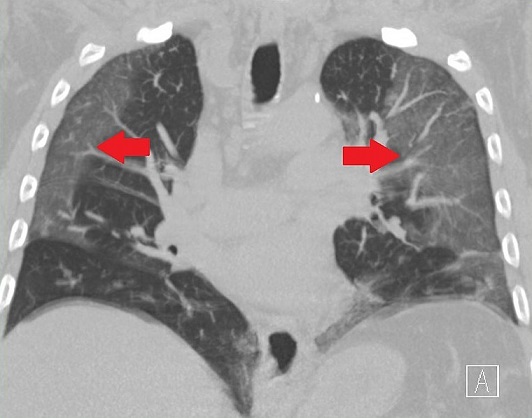

จินตงเยียน ชี้แจงว่าภาพเอกซเรย์ปอดมีฝ้าสีขาวจำนวนมากที่แชร์ทางสื่อสังคมออนไลน์ คือ ภาพเอกซเรย์ปอดที่บ่งบอกการมีอยู่ของรอยโรคชนิดที่เรียกว่า Ground-glass opacity (GGO) ซึ่งมีชื่อในภาษาไทยว่า รอยทึบแบบกระจกฝ้า หรือ ฝ้าจาง

GGO คือรอยโรคในปอดที่พบได้มากในผู้ป่วยโควิด-19 ที่มีอาการไวรัสลงปอด โดยผลเอกซเรย์หรือ CT Scan จะพบฝ้าสีขาวจางที่บริเวณปอด โดยภาพเอกซเรย์ปอดปกติจะเป็นสีทึบ แต่ปอดที่มีของเหลวหรือพังผืดเข้าไปแทนที่อากาศ ทำให้ปอดมีความหนาแน่นที่เพิ่มขึ้น เมื่อทำการเอกซเรย์ปอด ภาพที่ออกมาจะเปลี่ยนจากสีทึบกลายเป็นสีขาวจาง

ข้อมูลทางการแพทย์ระบุว่า ฝ้าจางชนิด GGO หากปล่อยให้ลุกลามอาจเป็นอันตรายถึงชีวิต และยังสามารถเกิดได้แม้แต่ผู้ติดเชื้อโควิด-19 ที่ไม่มีอาการ อย่างไรก็ดี รอยฝ้าจางสามารถหายได้เองเมื่ออาการป่วยทุเลาลง และจะไม่ส่งผลเสียต่อปอดในระยะยาว

จินตงเยียน ย้ำว่า โอกาสที่ผู้ติดเชื้อไวรัสโอไมครอนจะมีฝ้าจางชนิด GGO ที่ปอดเกิดขึ้นได้ยาก ส่วนการเกิดฝ้าจางจำนวนมากจนปอดกลายเป็นสีขาวทั้งหมดยิ่งพบได้ยากยิ่งกว่า การฉีดวัคซีนอย่างเหมาะสมและการใช้ยาต้านไวรัสอย่างทันท่วงทีเมื่อพบการติดเชื้อ ช่วยป้องกันความเสียหายของปอดจากการเกิดฝ้าจางชนิด GGO ได้